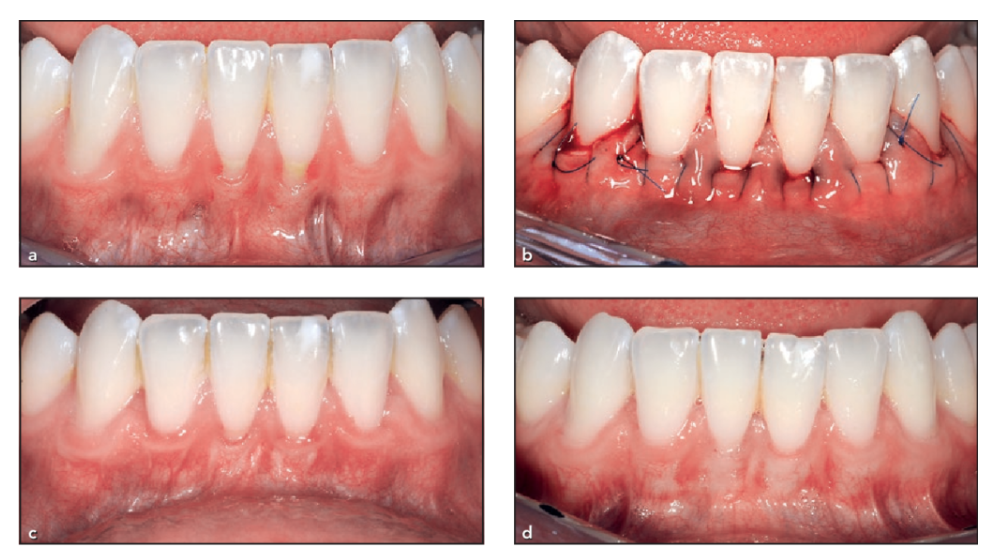

A connective tissue graft is the most common graft recommended to cover up exposed tooth roots. During this procedure, we make a small incision into the roof of your mouth, called the upper palate, to create a flap of skin. Next, we can remove some tissue from underneath the flap, called sub-epithelial connective tissue.

Once removed, the tissue is stitched around the gum, hiding the exposed tooth root. Treatment is completed by closing up the flap in your upper palate with stitches.

What to Expect During Gum Graft Surgery?

Before we carry out your surgery, we will numb your teeth and gums in the area treated using local anesthetic. Alternatively, you can discuss sedation dentistry during your initial visit with our periodontist.

Treatment is very straightforward and follows the steps below.

- Once you are comfortable and relaxed, our periodontist will make a small incision to create a tiny flap in the gums.

- They will clean the tooth roots thoroughly before harvesting the gum graft. The surgery site is then stitched shut, or we will place a periodontal dressing to protect it.

- Once the gum grafting material is harvested, it is placed over the exposed tooth roots and stitched into position.